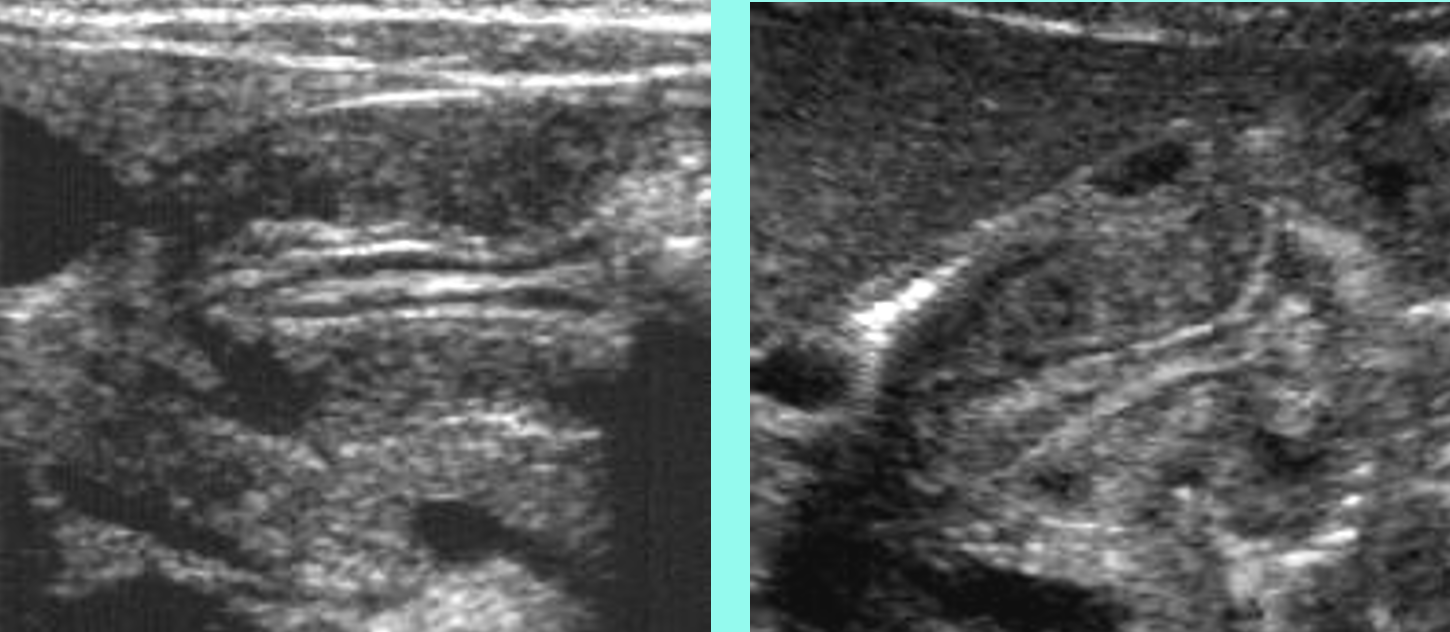

cervix sign in transverse indicating hypertrophic pyloric stenosis (HPS)

what is shown?

target sign in longitudinal plane indicating hypertrophic pyloric stenosis (HPS)